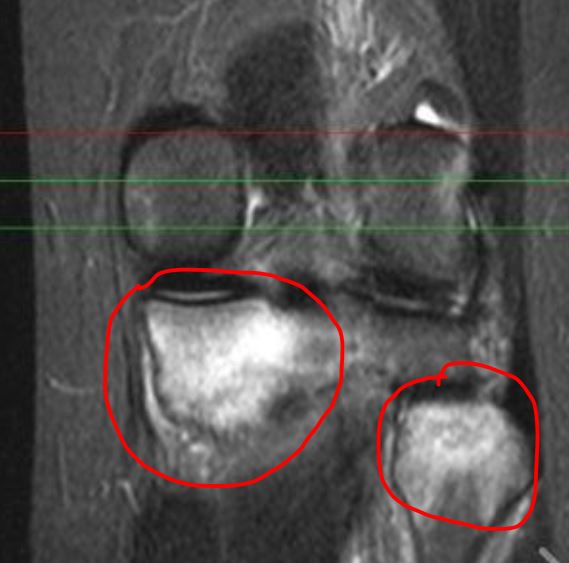

中年女性,某天一口气跑了四五公里,然后就出现了膝关节疼,自己没在意也不休息,第二天早上接着跑,然后第三天又快走,最后膝关节疼痛下不了地。没办法,到医院就诊,照了个核磁MRI发现关节内侧胫骨平台大面积水肿,关节积液。

核磁片上大面积骨水肿表现

女,20岁,长期没有活动的情况,猛烈地参加一次长跑运动后 ,主诉出现双侧内侧胫骨疼痛。在双侧胫骨中,内侧近端应力性骨折是明显的。用手指一按压膝关节内侧平台明显压痛! MRI提示双膝关节内侧胫骨平台骨水肿(骨挫伤)